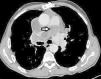

73-year-old patient with a history of pericardial hydatid cyst surgically resected 11 years ago who has chronic dyspnea since 6 months. On physical examination, the patient presented tachypnea and dyspnea. The chest x-ray showed a right hilar opacity. Thoracic CT scan (Fig. 1) showed a cystic filling defect of the main pulmonary artery and of right pulmonary artery. The echocardiography showed enlarged pulmonary arteries, enlarged chambers of the right heart and elevated pulmonary systolic pressure estimated at 80mm hg. Serologic tests of hydatid cyst were positive. The diagnosis of chronic pulmonary artery hydatid cyst was decided by the patient's history of pericardial hydatid cyst, thoracic CT scan, enlarged pulmonary arteries with elevated pulmonary systolic pressure and positive serology tests. A surgery was indicated but was refused by the patient. Therefore, a medical treatment was initiated (albendazole).